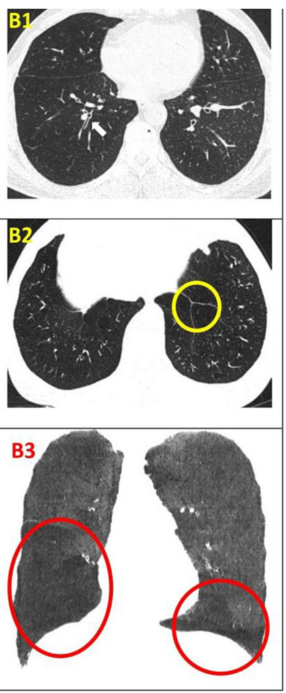

影像學(xué)檢查改善:CT 值在 - 1000 至 - 951 比例有所下降,Class4( % ) 亦明顯下降,故肺氣腫較治療前好轉。附圖為雙源 CT 肺實(shí)質(zhì)分析軟件,深藍色表示 CT 值在 -1000 至 - 951,治療后較治療前深藍色面積明顯縮小。

干細胞移植前后的肺部CT檢查對比

影像學(xué)檢查:對于患者 #2902,定量分析顯示基線(xiàn)時(shí)總體肺氣腫面積比為 12.75%,移植后 24 周降至 10.02%。在患者 #8009 中,肺氣腫面積比值從基線(xiàn)的 10.85% 下降到移植后 12 周的 9.08%。CT 圖像的三維可視化顯示,肺氣腫的減輕在下葉比在上葉更明顯。

患者 #2902 自體 P63 細胞移植前和后 24 周連續肺部 CT 圖像的三維可視化。